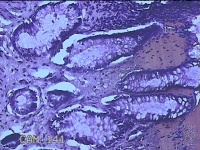

性别

男

年龄

40岁

临床诊断

混合痔

一般病史

反复肛门肿物突出15年。

标本名称

肛门肿物

大体所见

灰白暗红色肿物0.7x0.5x0.2cm一个,表面糜烂。

脱水、透明,浸蜡、脱蜡效果不佳,制片质量差。